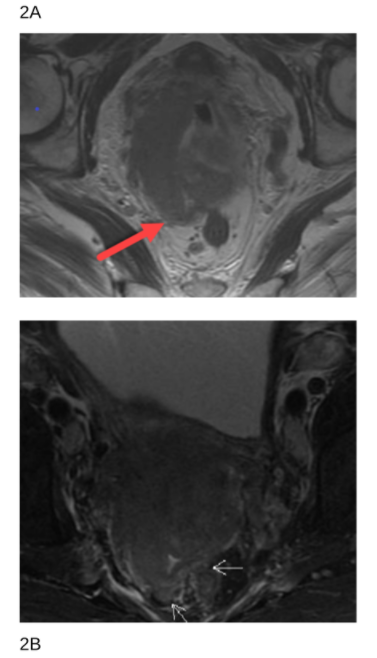

76 yr old female with stage IVA cervical squamous carcinoma with PA and right pelvic nodes, mesorectal pelvic nodes as well as right hydronephrosis, bilateral parametrial involvement and rectal wall invasion without a definite fat plane at the lower cervical mass. Definitive chemoradiation with cisplatin, immunotherapy and radiation was recommended after a multidisciplinary discussion.

Figure 2A. and 2B. MRI images with mesorectal invasion, arrow pointing toward posterior invasion.